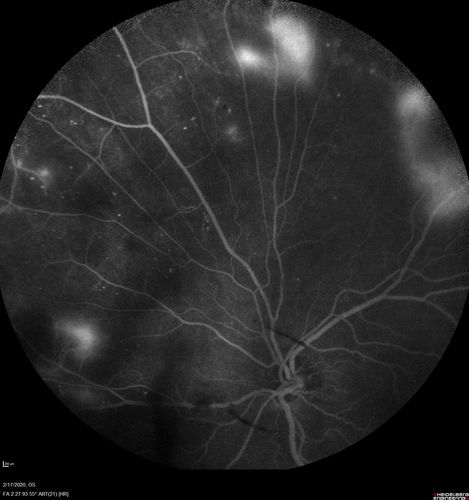

PDR and Vitreous Hemorrhage - High Risk Left Eye - Low Risk Right Eye

50 year old man with type I diabetes mellitus for 26 years. New Vitreous Hemorrhage in the left eye. Both eyes have NVE. Both also have foveal hypoplasia